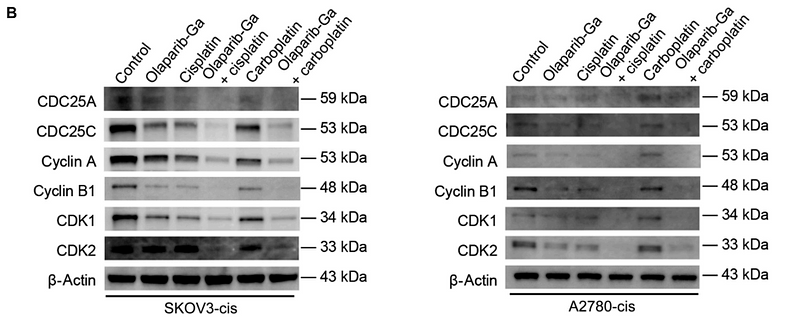

Nanoengineered Gallium Ion Incorporated Formulation for Safe and Efficient Reversal of PARP Inhibition and Platinum Resistance in Ovarian Cancer

Author:

PMID: 36930754

期刊: Research

应用: WB

反应种属: Human

发表时间: 2023 Mar

-